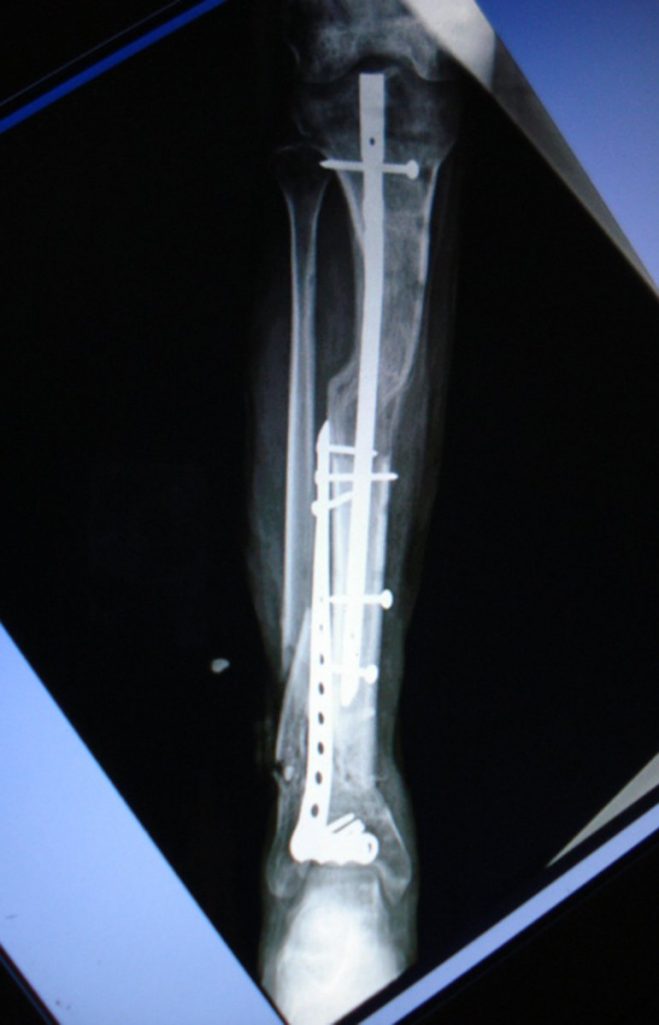

La técnica de alargamiento óseo se consigue con la colocación de una barra y tornillo, así como una esponja que ayudan a la regeneración de tejidos, informó en un comunicado el Instituto Mexicano del Seguro Social.

La doctora Fryda Medina Rodríguez, Directora General de la UMAE, quien encabeza el equipo de cirugía, explicó que esta técnica consiste en varios procedimientos, primero se retira el tejido muscular muerto, después se coloca una barra y un tornillo -que permanecen fijos a la extremidad-, y se realiza una incisión en la parte superior del hueso.

Posteriormente, colocan una esponja que ayuda a la regeneración de los tejidos al empujar la masa muscular sin obstruir los vasos sanguíneos, y se cubre con piel el tejido expuesto.

Explicó que la elongación ósea permite que el hueso se alargue un milímetro por día, al hacer girar el tornillo 45 grados cada seis horas, día y noche, acción que el paciente debe realizar una vez que es dado de alta del hospital.